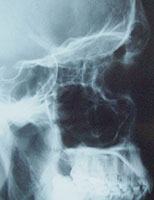

Poskiontelotulehdus todetaan tyypillisesti ultraääni-, röntgen- tai CT-kuvien perusteella.

röntgensäteet läpäisevät onton tilan helposti. Tulehduksissa onteloiden limakalvot ovat turvonneet tai onteloissa

on nestettä. Röntgenkuvissa tulehtuneet alueet näkyvät vaaleina alueina ilmavien alueiden erottuessa tummina.

Ontelot erottuvat erityisen hyvin CT-kuvauksessa, mutta sitä käytetään yleensä vain suunniteltaessa sivuonteloiden

kirurgisia toimenpiteitä.